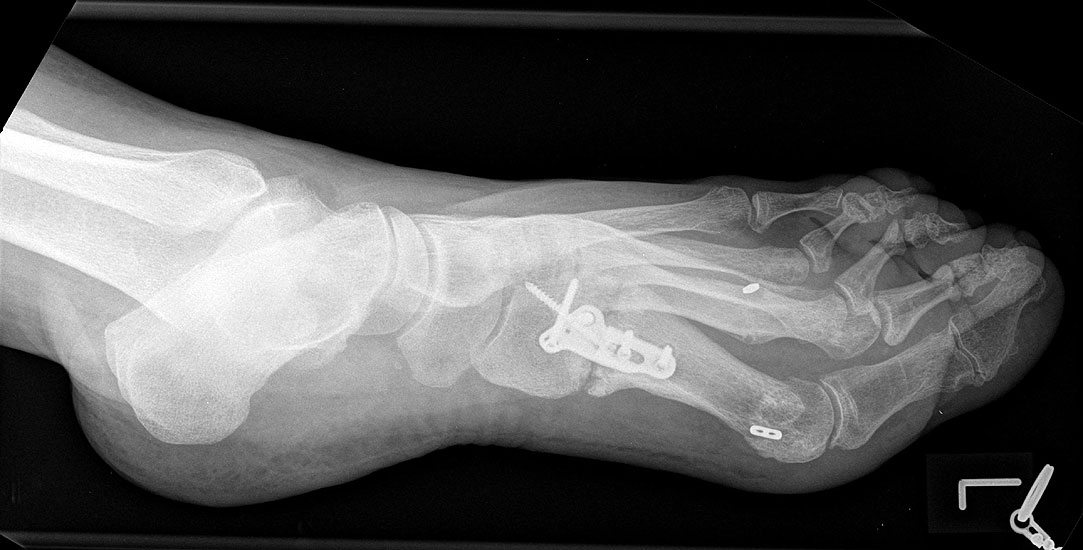

2) Rezidiv bei insuffizienter operativer Technik:

Die dorsoplantaren Röntgenaufnahmen zeigen eine Open-wedge Technik mit der normalerweise ein erhöhter intermetatarsaler Winkel gut zu korrigieren ist (Abbildung 3). Die Wirksamkeit einer Basisosteotomie ist umso größer, je proximaler diese durchgeführt wird. Je weiter distal die Osteotomie, umso geringer die Korrektur. Auf den postoperativen Bildern ist der distal unverändert große Abstand zwischen Metatarsale I und Metatarsale II erkennbar, bei gleichzeitiger Subluxation des Großzehengrundgelenks und dezentrierten Sesambeinen. Darüber hinaus finden sich initiale degenerative Veränderungen im Großzehengrundgelenk. Klinisch bestand eine hohe Weichteilspannung, bei verkürzter Extensor- und Flexor hallucis longus Sehne.  Daher wurde ein verkürzendes Verfahren zur Revision gewählt (Abbildung 4). Die Lapidusarthrodese stellt ein sehr zuverlässiges Verfahren zur Behandlung von Hallux valgus Rezidiven dar 9. Die Fusion des Tarsometatarsale-I-Gelenks kombiniert Stabilität mit einem hohen Korrekturpotenzial. Aufgrund der verfahrensimmanenten Verkürzung des ersten Strahls und der in diesem Fall bereits präoperativ vorhandenen Transfermetatarsalgie wurde die Entscheidung für eine verkürzte Weil-Osteotomie am zweiten bis fünften Strahl gefällt. Die Kombination beider Verfahren führte zu einem homogenen Metatarsale-Index und zu einer gleichmäßigen plantaren Druckverteilung 10. Die Hallux valgus interphalangeus Fehlstellung wurde mit einer Akin-Osteotomie korrigiert.